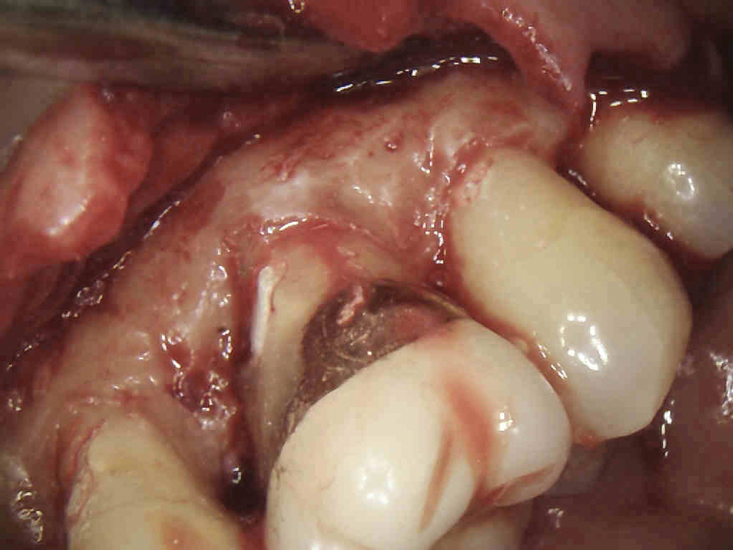

(3.) The initial surgical exposure revealed defects coronal to the crestal bone that were filled with granulation tissue and consistent with ECR.

Figure 3

(4.) The granulation tissue was removed in its entirety, and the defects were treated with a 90% TCA solution.

Figure 4

The surgical repair of ECR lesions is relatively straightforward. First, a sulcular incision should be created to develop a full-thickness flap that allows for complete visualization of the resorptive defect. Subsequently, all of the resorptive tissue should be removed. Curette instrument options for resorptive tissue removal may include appropriately sized excavators, scalers, or a diamond bur in a high-speed handpiece. Next, the resorptive cavity should be cleaned, and any areas of thin dentin that prevent access to the depth of the lesion should be removed with a high-speed bur or an ultrasonic scaler. If the margin of the resorptive defect sits at the crestal bone, judicious removal of the crestal bone via crown lengthening may be necessary to avoid biologic width violation.6

Once prepared, the resorptive cavity should be treated topically with a 90% trichloroacetic acid (TCA) solution. TCA serves to eliminate any remaining clastic cells, which are known to tunnel through the dentin beyond the visible cavity margins.5 Because TCA is quite caustic, to avoid injury, care must be taken to prevent it from accidentally being applied to the bone or soft tissue.8 Place a small amount of TCA in a small glass dappen dish and apply it to the resorptive lesion with a large absorbent paper point or small cotton pellet.5 TCA causes coagulation necrosis of any residual resorption tissue; however, this effect is nonspecific, so it is crucial to apply it carefully because it can cause chemical burns to the oral mucosa or skin.8